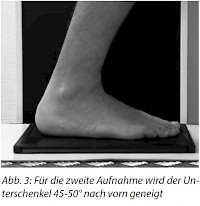

2. Aufnahme (Abb. 2-3)

Nach der 1. Aufnahme bleibt der Patient mit der Fußsohle auf der Kassette stehen und nimmt denanderen Fuß einen Schritt nach vorne. Das Knie der zu untersuchenden Seite leicht anbeugen, damit der Unterschenkel schräg nach vorn geneigt ist und mit der Fußsohle einen Winkel von 45-50° bildet.

Zentrierung: senkrecht über 10° von hinten auf das Fersenbein und Kassettenmitte.

Strahlengang: dorsoplantar Einblenden auf Objekt, d. h. auf das Fersenbein bis zum Unterschenkel

Achtung: Die zweite Aufnahme erfordert bei einem Erwachsenen je nach Konstitution zwischen mind. 3 Belichtungspunkten und 6 Belichtungspunkten mehr Schwärzung!